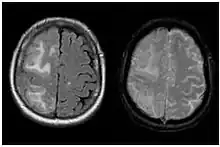

| Two MRI scans demonstrating the difference between ARIA-E (left) and ARIA-H in the parietal region (right) | |

Amyloid-related imaging abnormalities (ARIA) are abnormal differences seen in magnetic resonance imaging of the brain in patients with Alzheimer's disease. ARIA is associated with anti-amyloid drugs, particularly human monoclonal antibodies such as aducanumab.[1] There are two types of ARIA: ARIA-E and ARIA-H. The phenomenon was first seen in trials of bapineuzumab.[2]

ARIA-H refers to cerebral microhaemorrhages (mH), small haemorrhages on the brain,[5] often accompanied by hemosiderosis.[1] mH are usually seen as small, round and low intensity lesions and are small haemosiderin deposits. Some studies define mH as being less than or equal to 10mm, while others define the cut-off as ≤ 5mm.[1] The prevalence of mH in healthy elderly people is approximately 6%, but this value increases to between 50% and 80% in elderly people with cerebrovascular disease.[6]